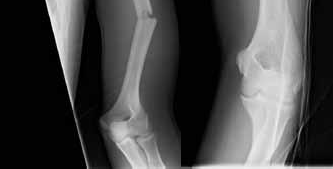

Question 20:

A 6-year-old girl falls from monkey bars and sustains a widely displaced extension-type supracondylar fracture of the distal humerus. On physical examination prior to reduction, she is unable to flex the interphalangeal joint of the thumb and the distal interphalangeal joint of the index finger, resulting in an inability to make an 'A-OK' sign. Which nerve is most likely injured?

Correct Answer: Anterior interosseous nerve (AIN)

Explanation:

The anterior interosseous nerve (AIN), a motor branch of the median nerve, is the most commonly injured nerve in extension-type supracondylar humerus fractures. It innervates the flexor pollicis longus (FPL) and the flexor digitorum profundus (FDP) to the index and middle fingers. Injury results in the inability to flex the IP joint of the thumb and DIP joint of the index finger, preventing the patient from making an 'OK' sign.